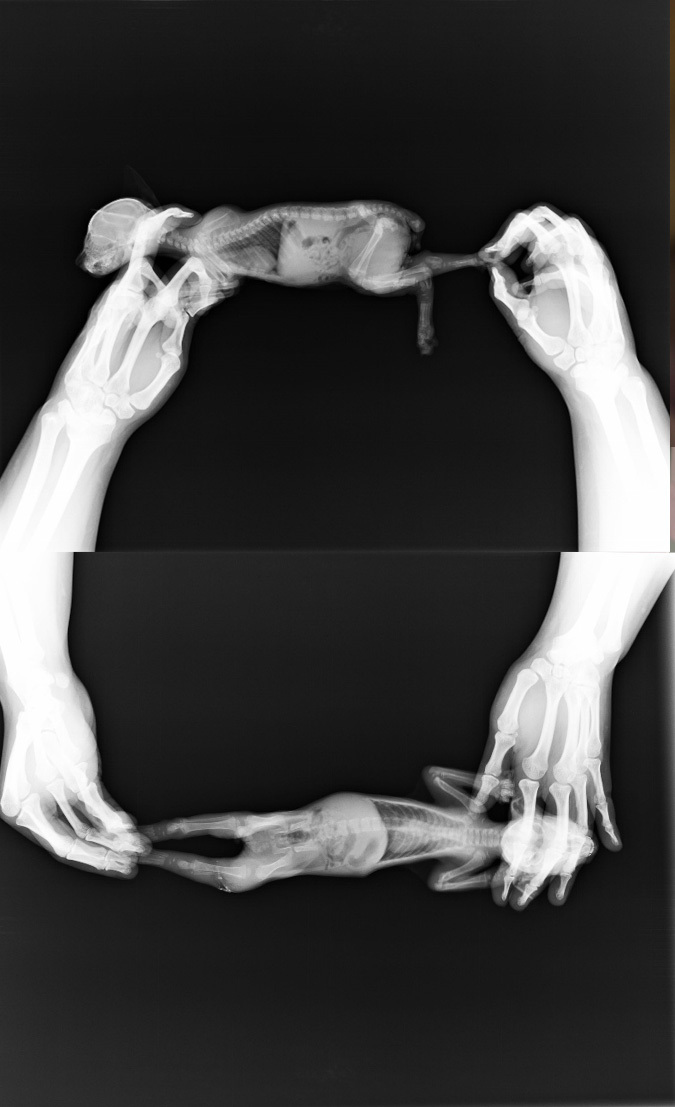

主題: 左腿似割傷右腿缺肉且營養不良的幼貓 申請者姓名: 羅心雅 花色: 申請日期: 2015-10-02 02:16:49 申請者部落格: 申請者臉書網址: http://facebook.com/xinya.luo 所在縣市/合作醫院: 台中市/春天動物醫院 治療費用: 10100元 需求人數: 12人 已結案 (2022-05-13 15:13:05) 報名人員: 蘇小優(已付款)、卓吟靜(已付款)、moca(已付款)、CHC(已付款)、Fox Yo(已付款)、Kevin J Shih(已付款)、Diamond(已付款)、Carrie(已付款)、徐粉粉(已付款)、Kenix(已付款)、Ray0322(已付款)、羅心雅(已付款)、 候補人員: 動物病情說明: 於住處之子母垃圾車旁看到此幼貓,當時牠已無力行走,雙眼佈滿眼膏黏住,左後腿以拖的方式爬行,給予食物 但無進食,抱起才發現左後腳有大割傷似斷掉的樣子,且呈紅腫狀,右後腳內側有磨傷缺肉的狀況.因狀況危急所以先送醫治療,因治療金額超出個人經濟能力,也是第一次就援不知如何求救,經由表姐告知貴會有醫助管道,於9/16經醫院介紹志工請教如何填寫申請資料,上傳貴會,之後小貓還要陸續進出醫院,煩請貴會幫幫忙. 動物近況說明: 9/13送至醫院發現雙眼已被眼屎及眼膏黏住,左後腳傷口被污物黏住,整隻腿部紅腫,右後腳內側有磨傷缺肉,就診後醫師說左後腳傷口有潰爛壞死肌肉出現空隙現象發出腐臭味,且左後腿整支發紅腫脹另有營養不良的狀況.施打消炎藥及營養針,對傷口進行灌洗.僅能食用嬰兒副食品罐頭(以針管餵食).

9/14眼部狀況恢復良好,眼膏流出狀況減緩,左腳腐臭味減緩,但仍有流水的現象,傷口走動時露出白色腐臭肌理,對傷口進行灌洗;右腳呈粉紅些許出水的嫩肉.開消炎藥回家自行餵食,並開始嘗試幼貓飼料和嬰兒副食搭配餵食.且因約出生20幾天,還不會自行排便,因此告知需引導排便.晚上引導排便,順利排大便1次及尿水1次.

9/16眼部已無流眼水及眼膏,雙眼清明,且胃口不錯(一餐可自行食用30顆幼貓飼料,一天約食7餐),順利排大便1次及尿水1次.左後腳腐臭味減少且呈現粉紅出水嫩肉,傷口開口處看得見骨頭及部份粉紅肉組織,右腳開始有大塊結疤硬塊.今日左後腳開始做清創敷藥包紮(開始要為期兩週的清創,每2日清創一次,視清創狀況,之後再進行縫合),右後腳給予藥劑自行擦拭,今日開消炎藥3日份(內含驅蟲藥),護士建議可開始使用貓砂.

9/18胃口不錯(一餐可自行食用30顆幼貓飼料(半軟),一天約食7餐),順利排大便2次(內有出現白色小點狀的蟲)及尿水2次.左後腳已無腐臭味,但敷藥紗布取下仍有乳白分泌物,因此今日仍以敷藥包紮,開消炎藥及抗生素早晚餵食,右腳大塊結疤硬塊脫落.型成小肉疤,繼續以藥劑擦拭傷口外圍,貓砂使用狀況良好,會自行使用貓砂.開始好奇環境,想跟到房門外了解環境狀況,會奔跑至跟前.

9/21胃口增加(一餐可自行食用40顆幼貓飼料(半軟),一天約食7餐),順利排大便3次(內仍出現少量白色小點狀的蟲)及尿水2次.左後腳敷藥紗布取下仍有乳白分泌物,因此今日仍以敷藥包紮,開消炎藥及抗生素早晚餵食;右腳型成小結疤,繼續以藥劑擦拭傷口外圍.會認人及討取食物,開始會攀爬且自微高處跳下.

9/23左後腳敷藥紗布取下些許乳白分泌物,傷口呈現血紅肌理組織,院長告知復元狀況良好,開時長肉,因此今日開始塗幫助肉芽生長的藥劑包紮,開消炎藥及抗生素早晚餵食,右腳小結疤,繼續以藥劑擦拭傷口外圍;一餐可自行食用40顆幼貓飼料,因出現愛咬東西的狀況,嘗試食用未泡水的幼貓飼料一餐可食用15~18顆硬,22~25顆半軟飼料,另補充一些水,一天約食7餐,順利排大便3次(已無出現白點,但排便有些稀狀)及尿水3次.開始喜歡窩人睡,跟人玩.

9/25左後腳敷藥紗布取下,傷口血紅肌理組織部份明顯縮小,外圍開時長出皮,繼續塗幫助肉芽生長的藥劑包紮,右腳小結疤,繼續以藥劑擦拭傷口外圍;一餐可自行食用40顆幼貓飼料,因出現愛咬東西的狀況,嘗試食用未泡水的幼貓飼料一餐可食用15~18顆硬,22~25顆半軟飼料,另補充一些水,一天約食7餐,順利排大便3次(已無出現白點,排便為條狀)及尿水3次.開始喜歡跟人行走,無人陪伴時會呼叫.

9/27左後腳敷藥紗布取下,傷口血紅肌理組織部份明顯縮小,外圍開時長出皮,繼續塗幫助肉芽生長的藥劑包紮,右腳小結疤,已可開始不用擦藥讓其自行癒合;一餐可自行食用40顆幼貓飼料,因出現愛咬東西的狀況,嘗試食用未泡水的幼貓飼料一餐可食用15~18顆硬,22~25顆半軟飼料,另補充一些水,一天約食7餐,順利排大便4次(排便為淡黃條狀)及尿水3次.已可自離地約30cm高跳上跳下玩耍.

經由醫生評估可居家照料也可節省住院費用.